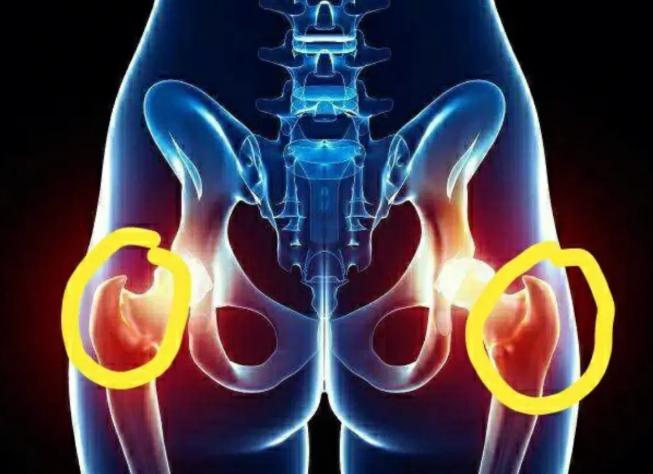

2、股骨头坏死引发的疼痛

在众多残疾性疾病中,股骨头坏死是比较严重的,也是十分常见的一种疾病,它是髋关节出现坏死的情况,受到各种因素的影响,是股骨头的血液供应不足。

如果情况比较严重的话,很有可能导致股骨头出现塌陷。而这种残疾性疾病最直接的表现就是髋关节出现疼痛,并且出现功能性的障碍。 股骨头坏死在早期的时候是没有任何症状的,即便是在x射线检查的过程中也不容易被发现,只有通过MRI检查才能查出股骨头坏死问题。

不过这股骨头坏死出现之前, 很有可能引起髋关节出现疼痛的问题,而且随着病情不断加重,还会导致人体行走困难,甚至必须要拄拐而行。

怎样判断股骨头是否出现坏死的情况呢? 其实可以通过翘二郎腿的方式进行自我检查,在翘二郎腿的时候,如果髋关节的前方出现明显的疼痛,或者根本无法翘起二郎腿, 说明这一关节出现了问题。